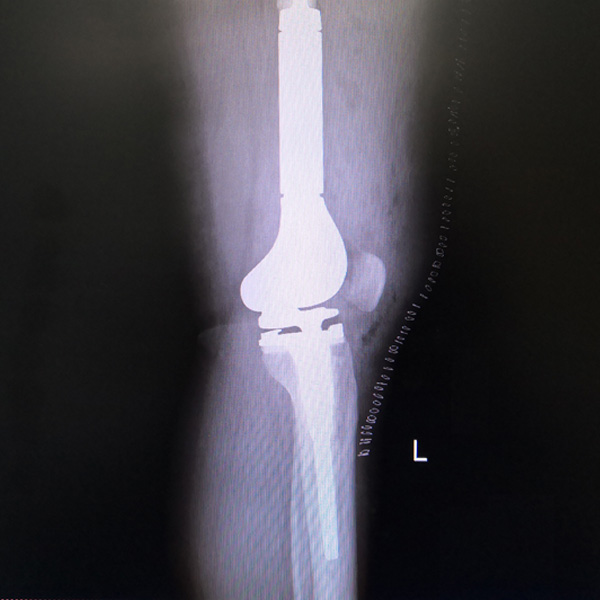

• 膝關節內翻膝關節內翻手術后手術前

膝關節內翻

患者劉某某,女66歲,左側膝關節嚴重內翻(俗稱的“羅圈腿”),疼痛到不能生活自理。經平臺推薦到哈爾濱醫科大學附屬第二醫院骨關節科就診,......